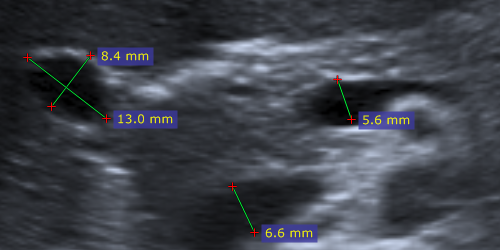

超声(US)图像中的测量

超声设备产生的 DICOM 图像通常包含经过校准的区域。根据区域类型,可以测量不同的参数。

下图为测量距离、速度和时间的示例截图。